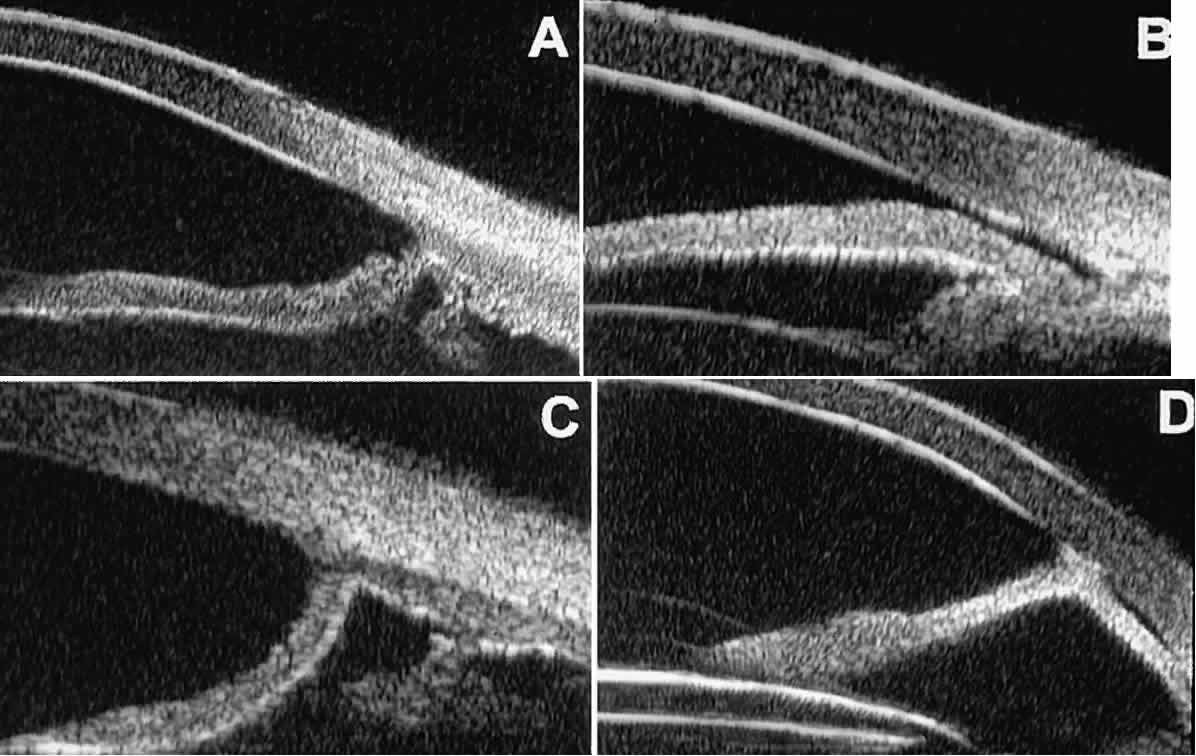

In open-angle glaucoma, UBM can be used to measure the anterior chamber angle in degrees, to assess the configuration of the peripheral iris, and to evaluate the trabecular meshwork (Fig. 9).2,4 The angle configuration can be graded and compared with gonioscopic findings. In certain patients with open-angle glaucoma, UBM can provide information that may be of some diagnostic value (Fig. 10). For example, in pigment dispersion syndrome (see Fig. 10A),6 UBM typically reveals posterior bowing of the peripheral iris (“q” configuration of peripheral iris by Spaeth classification5). In plateau iris syndrome (see Fig. 10B),7 UBM usually reveals abnormally steep anterior angulation of the peripheral iris (“s”configuration of peripheral iris by Spaeth classification5), insertion of the iris from the anterior ciliary body, and retroiridic projection of the ciliary processes. In eyes with peripheral anterior synechiae (see Fig. 10C and D), UBM can reveal the extent of iridocorneal adhesion even if the cornea is hazy or opaque.

Fig. 10. UBM features of special glaucoma cases. A. Pigment dispersion syndrome with posterior bowing of peripheral iris (“q” configuration by Spaeth gonioscopic grading system). B. Plateau iris syndrome with origin of iris from anterior surface of ciliary processes behind peripheral iris, slitlike narrowing of peripheral angle, and abrupt transition from steep peripheral iris to flat iris midzone. C. Broad peripheral anterior synechia with posterior bowing of nonadherent iris. D. Peripheral anterior synechia with aqueous-filled slit between site of iridocorneal adhesion and iris root after cataract extraction with implantation of posterior-chamber IOL.

In eyes with a narrow angle, UBM shows the extent of angle closure, reveals the depth of the anterior and posterior chambers, and identifies pathologic processes pushing the lens and iris forward (Fig. 11).2–4,8 UBM has been able to differentiate between primary angle closure (i.e., cases of angle closure without additional pathology responsible for the anterior lens-iris displacement [see Fig. 11A] and secondary angle closure due to processes such as lens swelling and dislocation (see Fig. 11B), massive hemorrhagic retinal detachment pushing the lens and iris anteriorly (see Fig. 11C), and multiple neuroepithelial cysts of the iridociliary sulcus (see Fig. 11D).

Fig. 11. Angle configuration in eyes with angle-closure glaucoma. A. Primary angle-closure glaucoma with anterior displacement of lens and iris. B. Angle closure secondary to swollen, cataractous lens (phakomorphic angle closure). C. Angle closure secondary to massive hemorrhagic retinal detachment; the subretinal blood is evident in the lower right corner of the photograph. D. Angle closure secondary to multiple peripheral iris cysts.